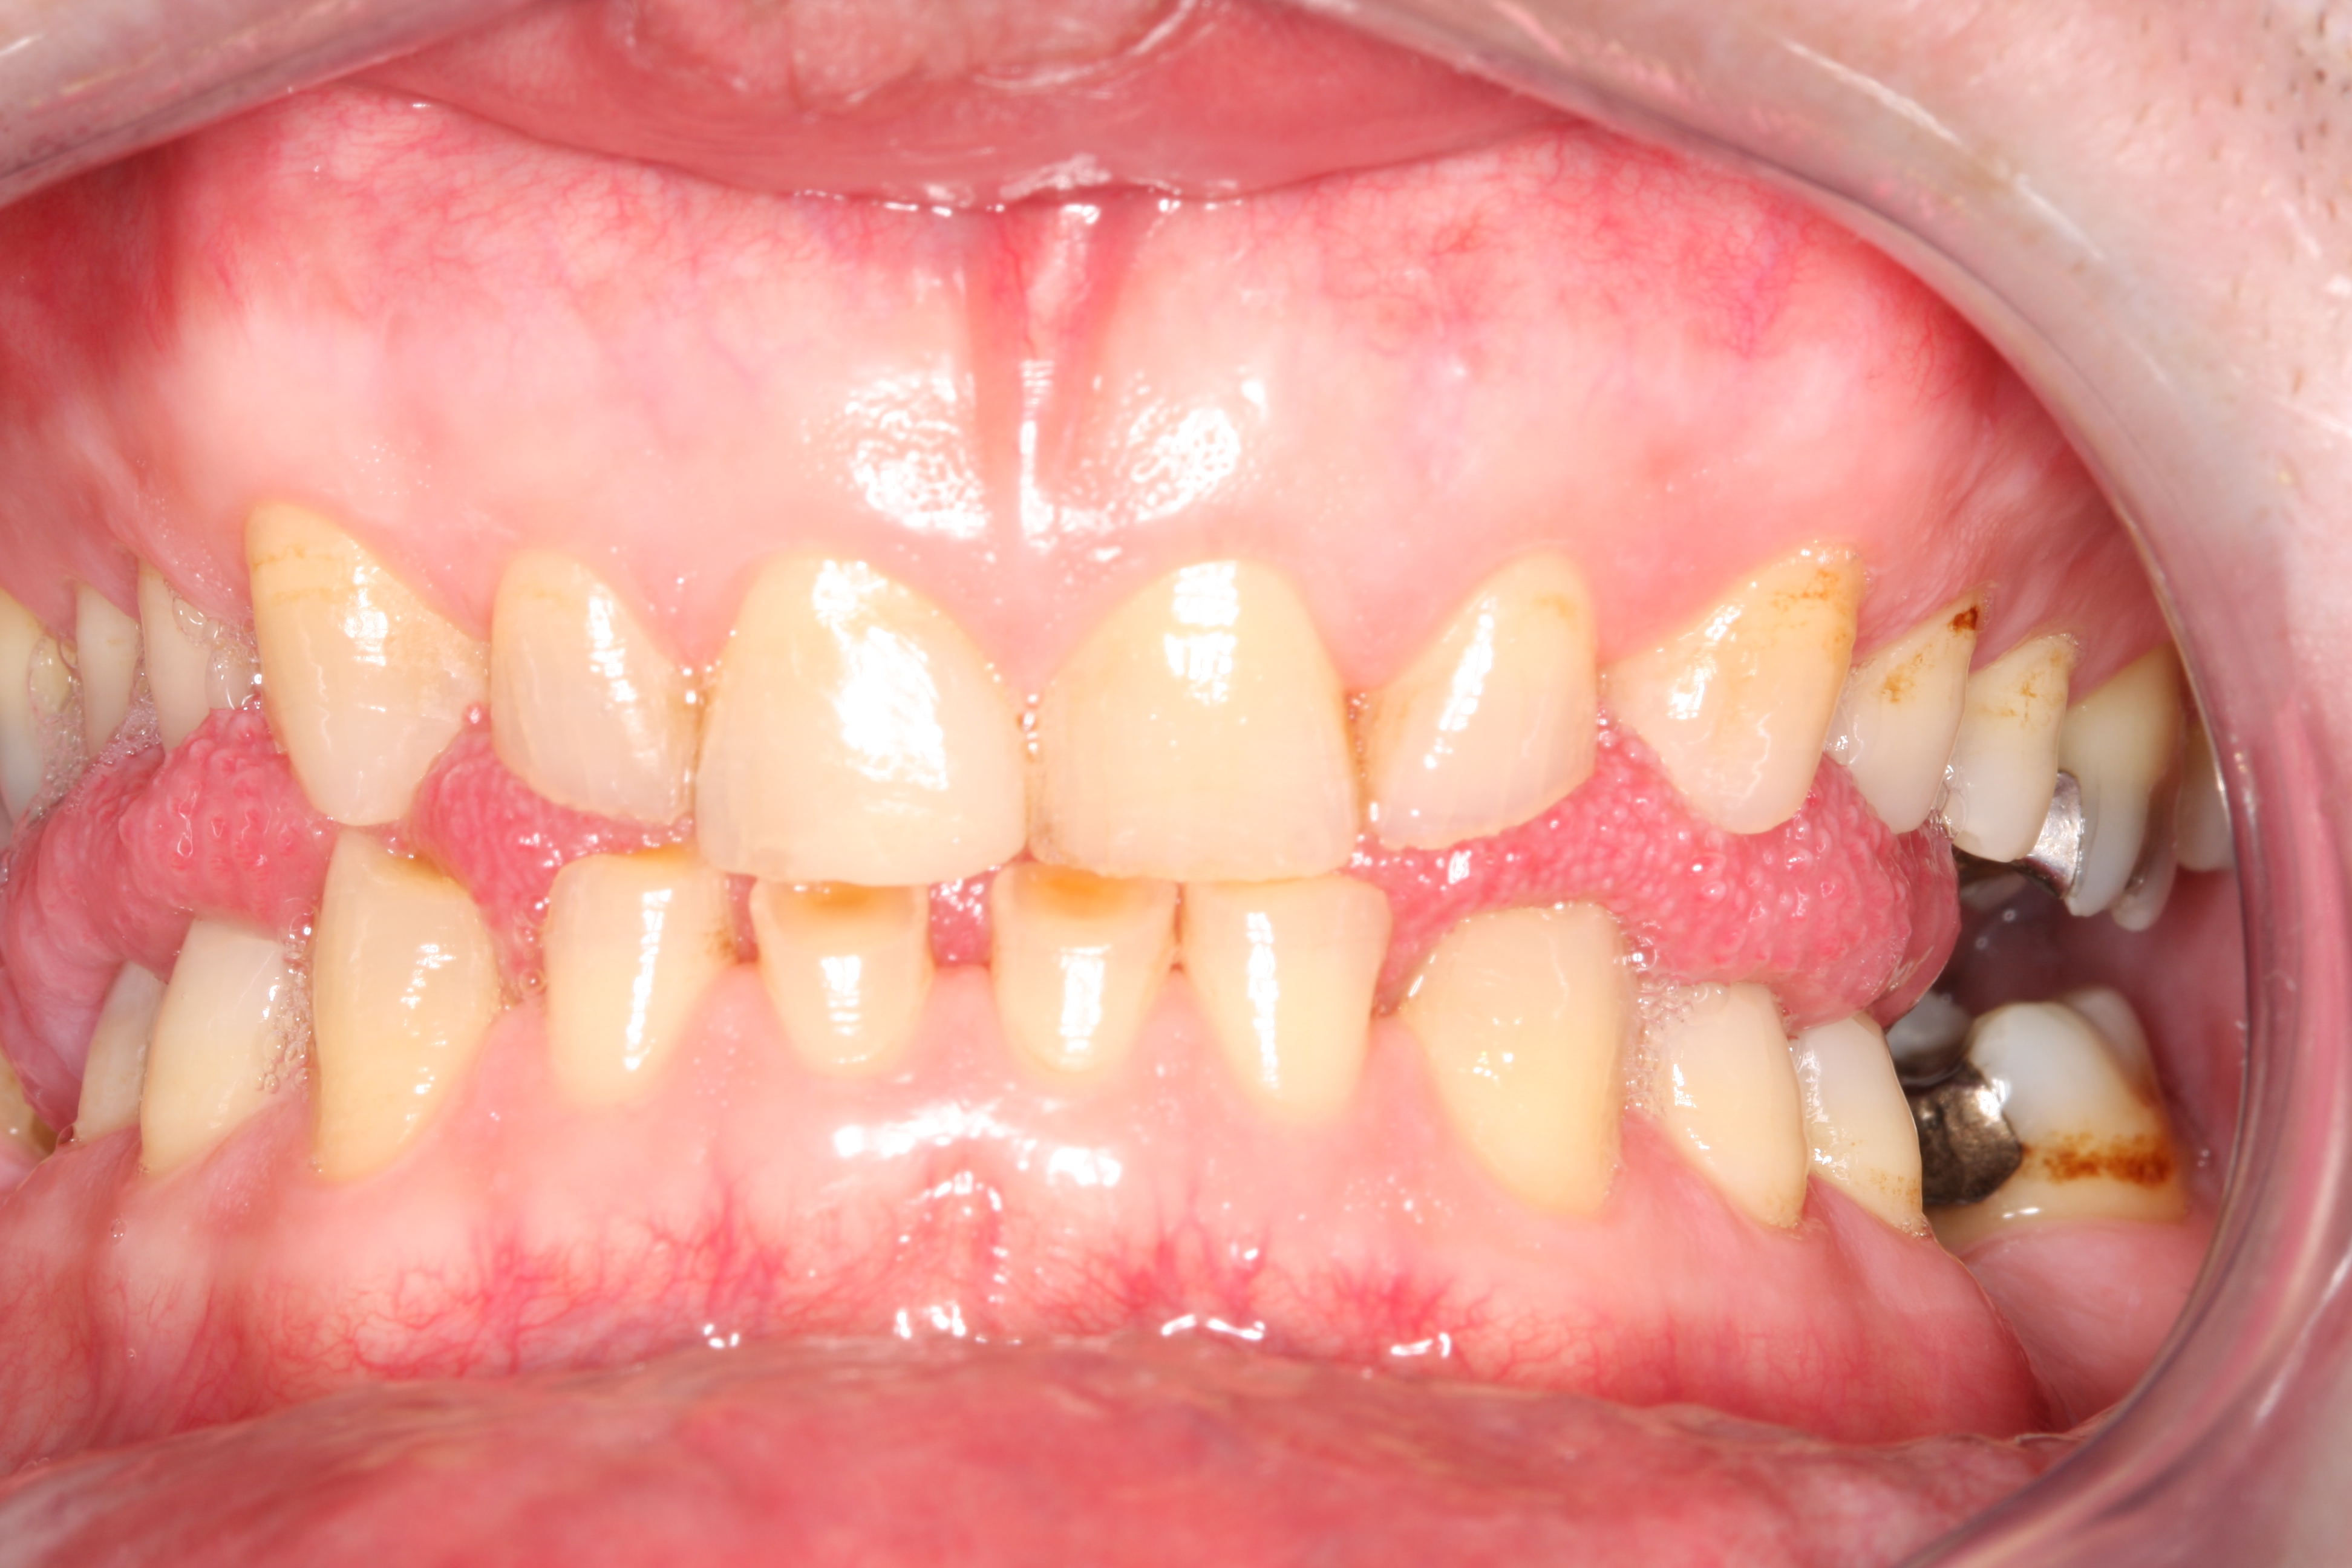

Dit zijn de voor en na fotos uit 2008:

In 2008 ben ik bij ACTA behandeld voor gebitsslijtage door bruxisme. De behandeling bestond toen uit het vervangen van alle vullingen, opbouw van kiezen, en het plaatsen van composiet facings op al mijn tanden. Ik was destijds zeer tevreden met het resultaat.